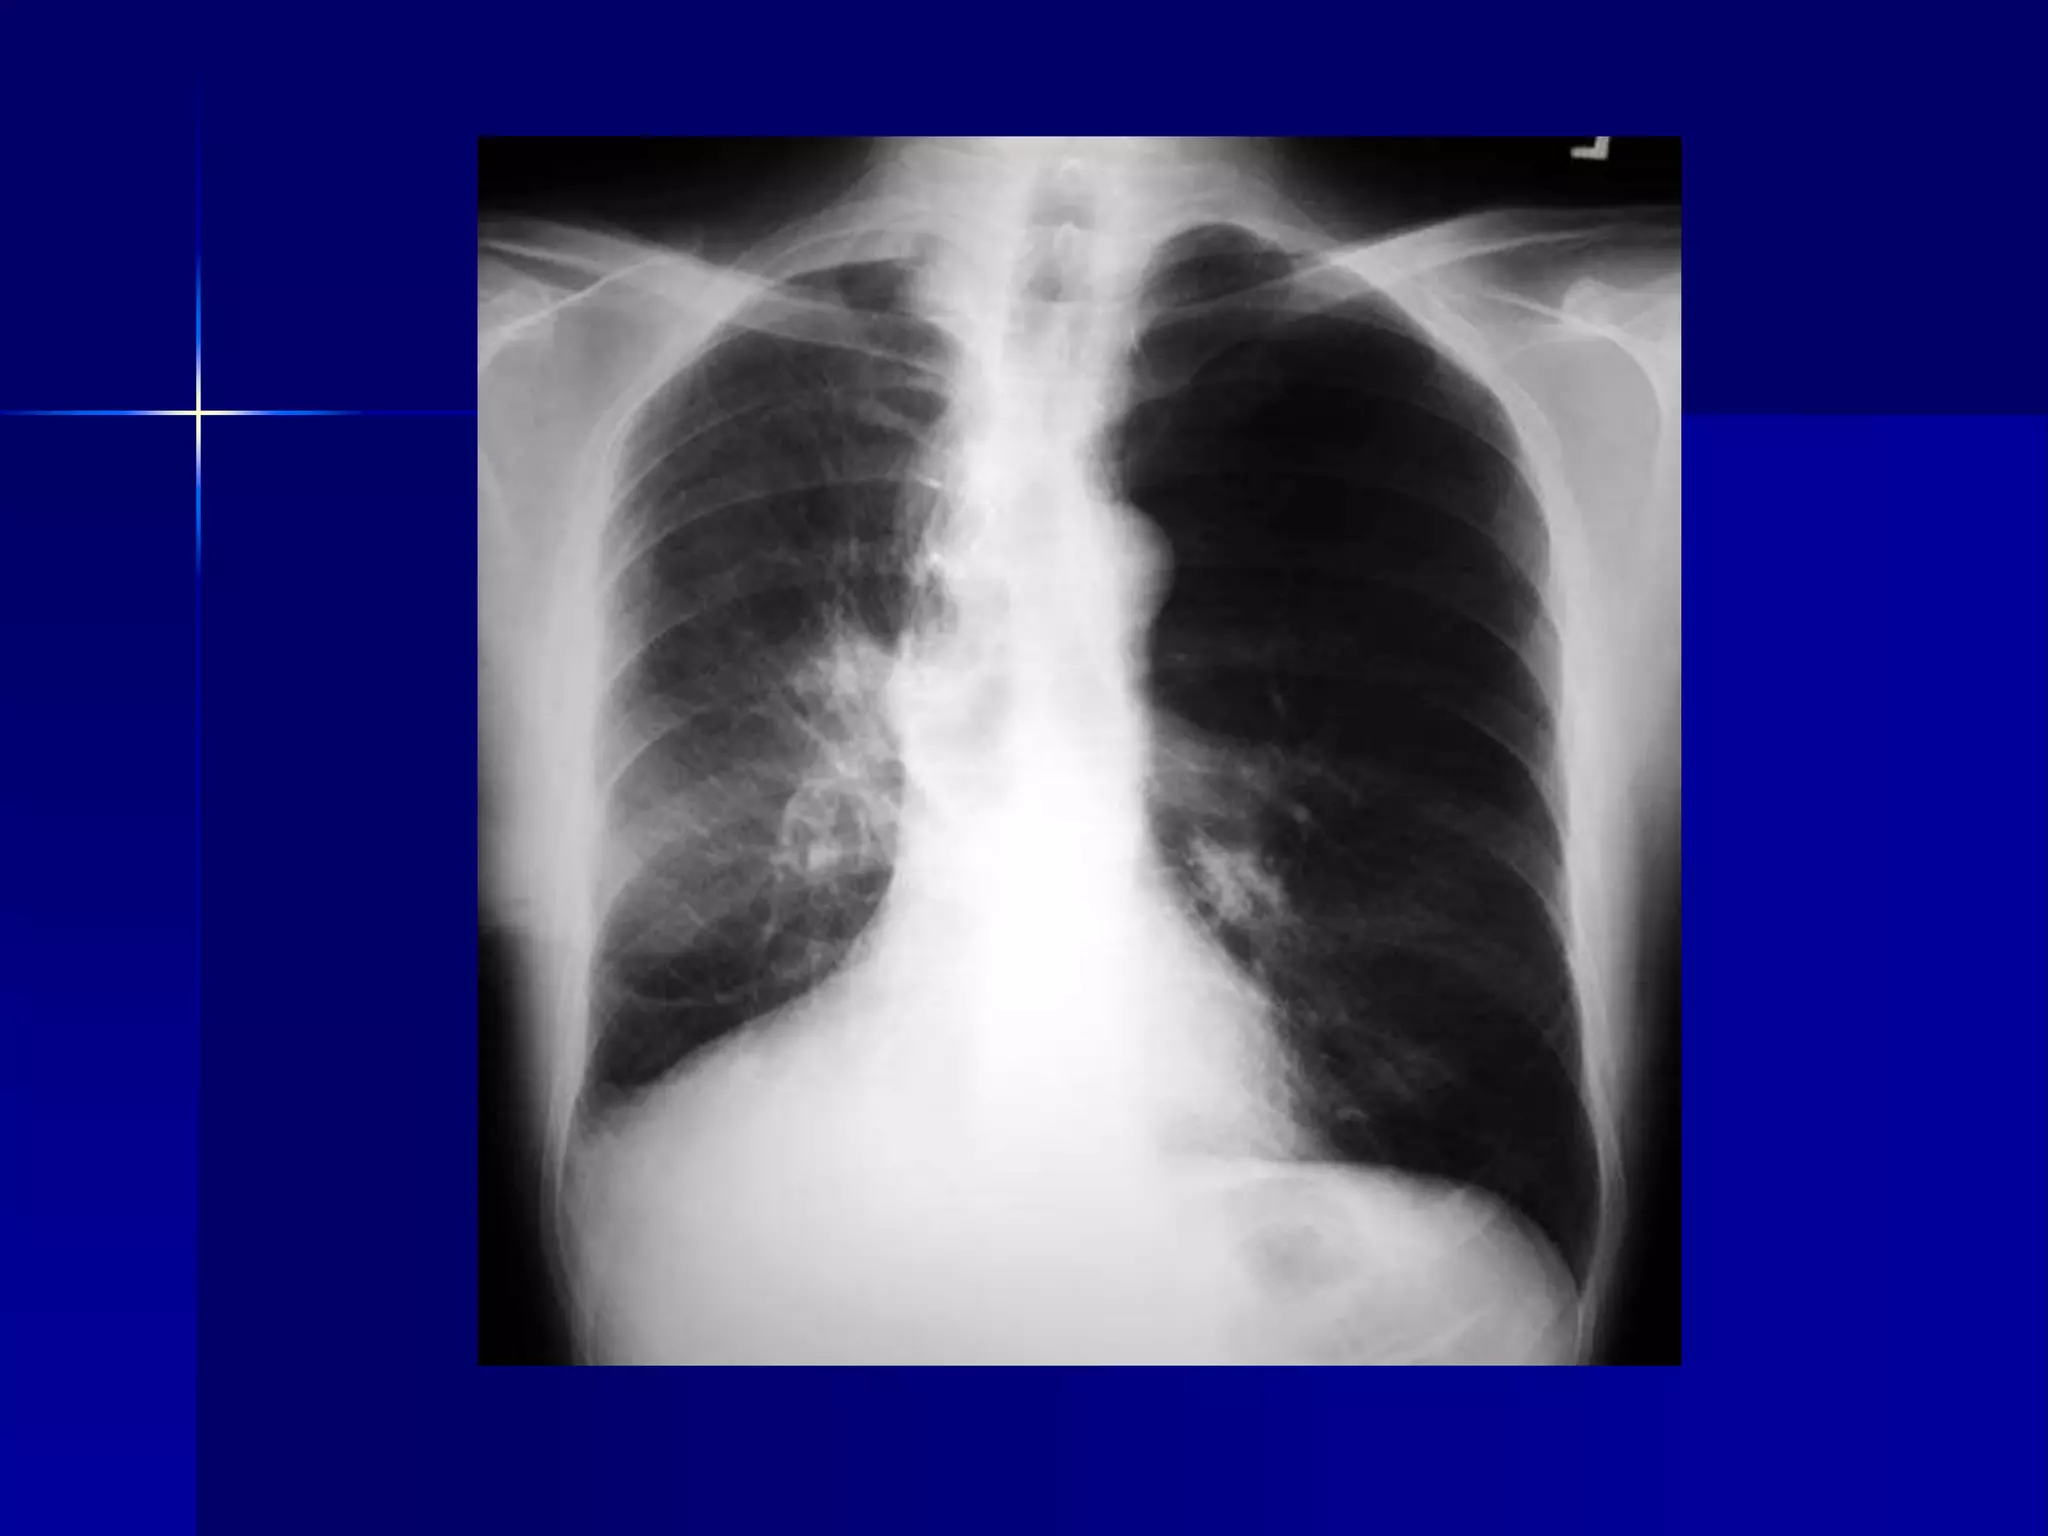

 Atelectasis Left Lower Lobe

 Inhomogeneous cardiac density

 Triangular retrocardiac density

 Left hilum pulled down